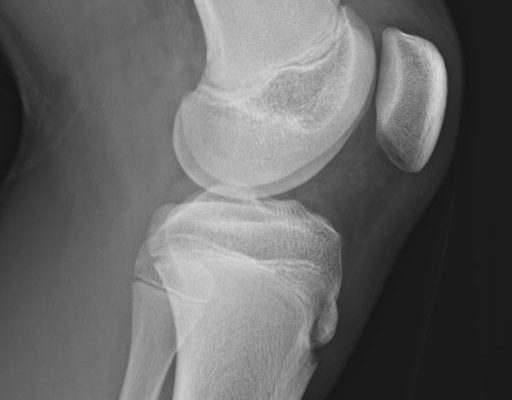

- ✅ Skręcenia lub niestabilności w kolanie (ACL, uszkodzonie łąkotki, uszkodzenie więzadeł MCL, LCL)

- ✅ Stanu po artroskopii kolana (np. szyciu łąkotki, meniscektomii łąkotki, rekonstrukcji więzadła ACL, osteotomii)

Nie, skierowanie nie jest wymagane. Jeśli posiadasz jakąkolwiek dokumentację medyczną (USG, RTG, rezonans magnetyczny, wypis ze szpitala), zabierz ją ze sobą – będzie ona bardzo pomocna w planowaniu terapii.